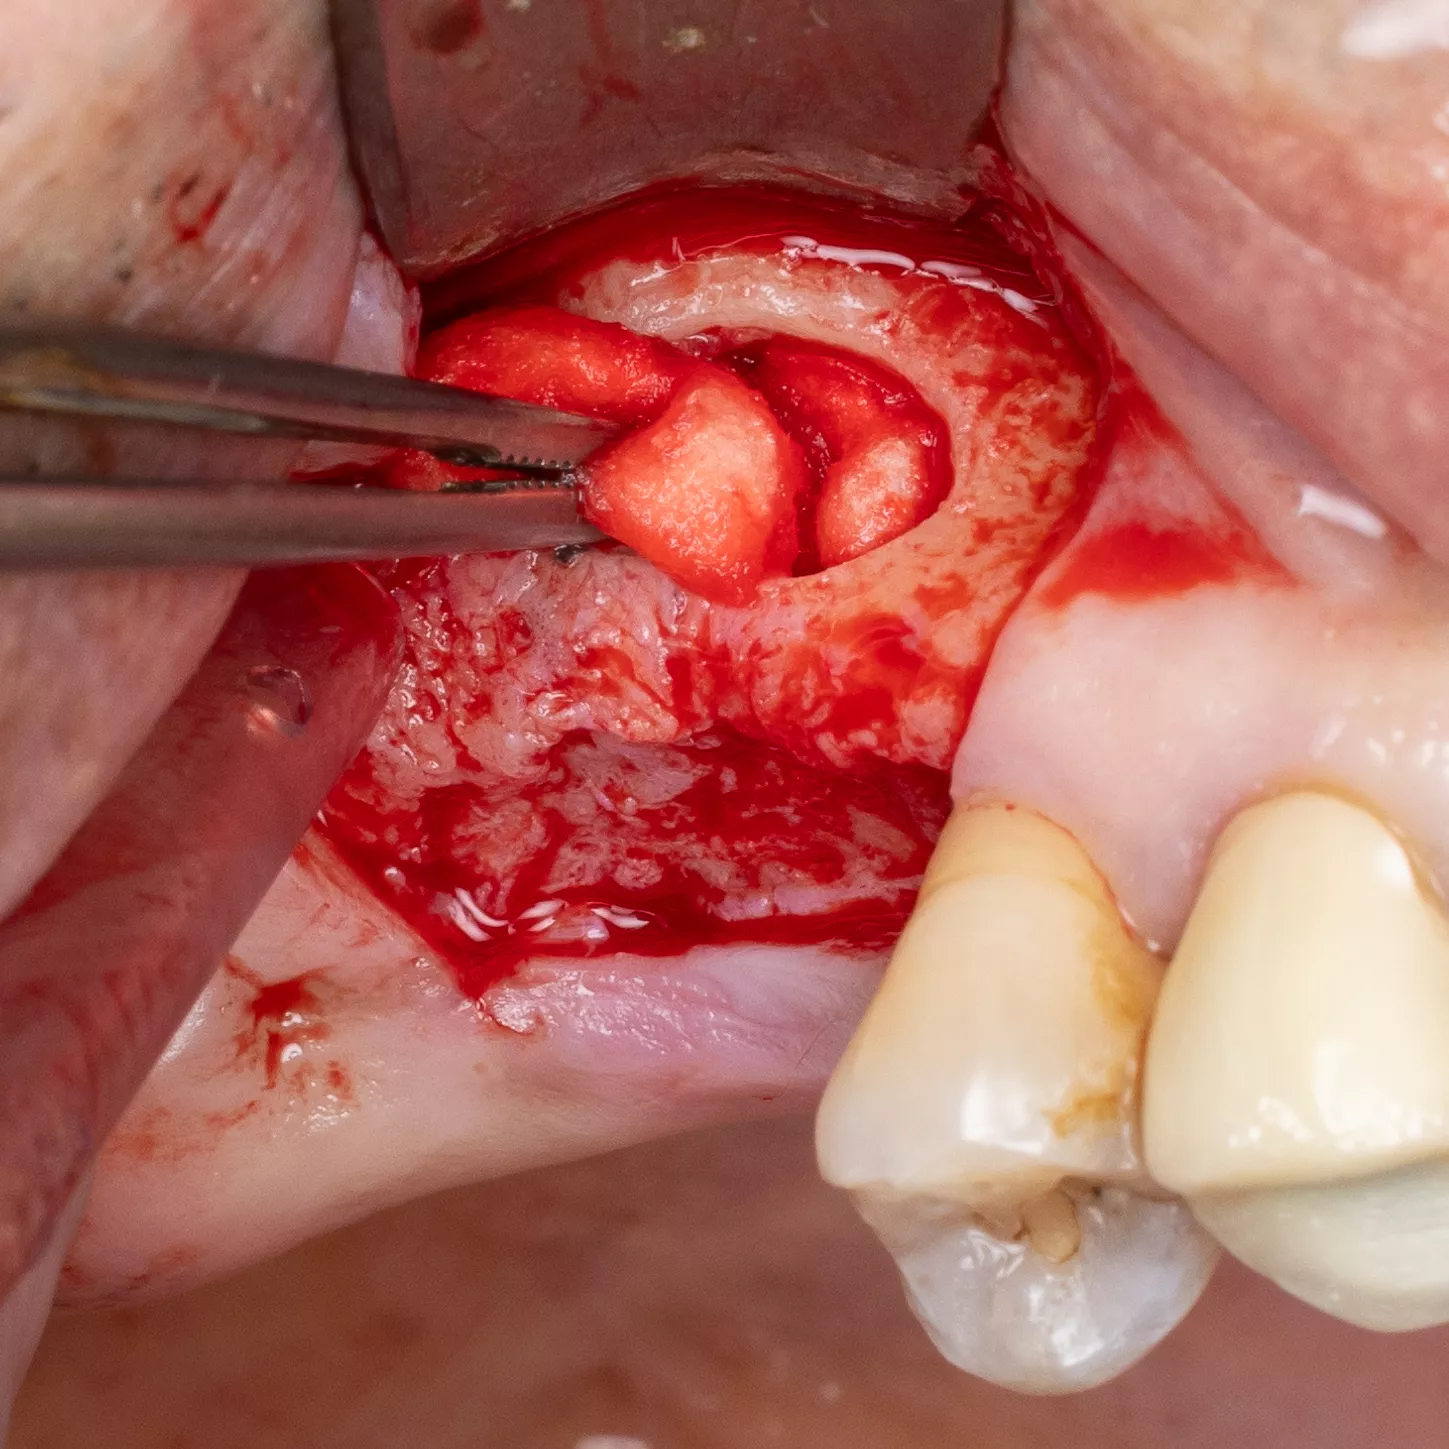

3. Flap detachment:

Crestal incision and diverging vertical discharges. Mucoperiosteal lift.

4. Sinus window : Subtractive osteotomy without preservation of the bone flap using a 2.5 mm diamond bur mounted on a surgical handpiece. The Schneiderian membrane (sinus mucosa) of slightly bluish grey color is exposed.

5. Initiation of lifting of the sinus mucosa through the inferior mesial window angle.